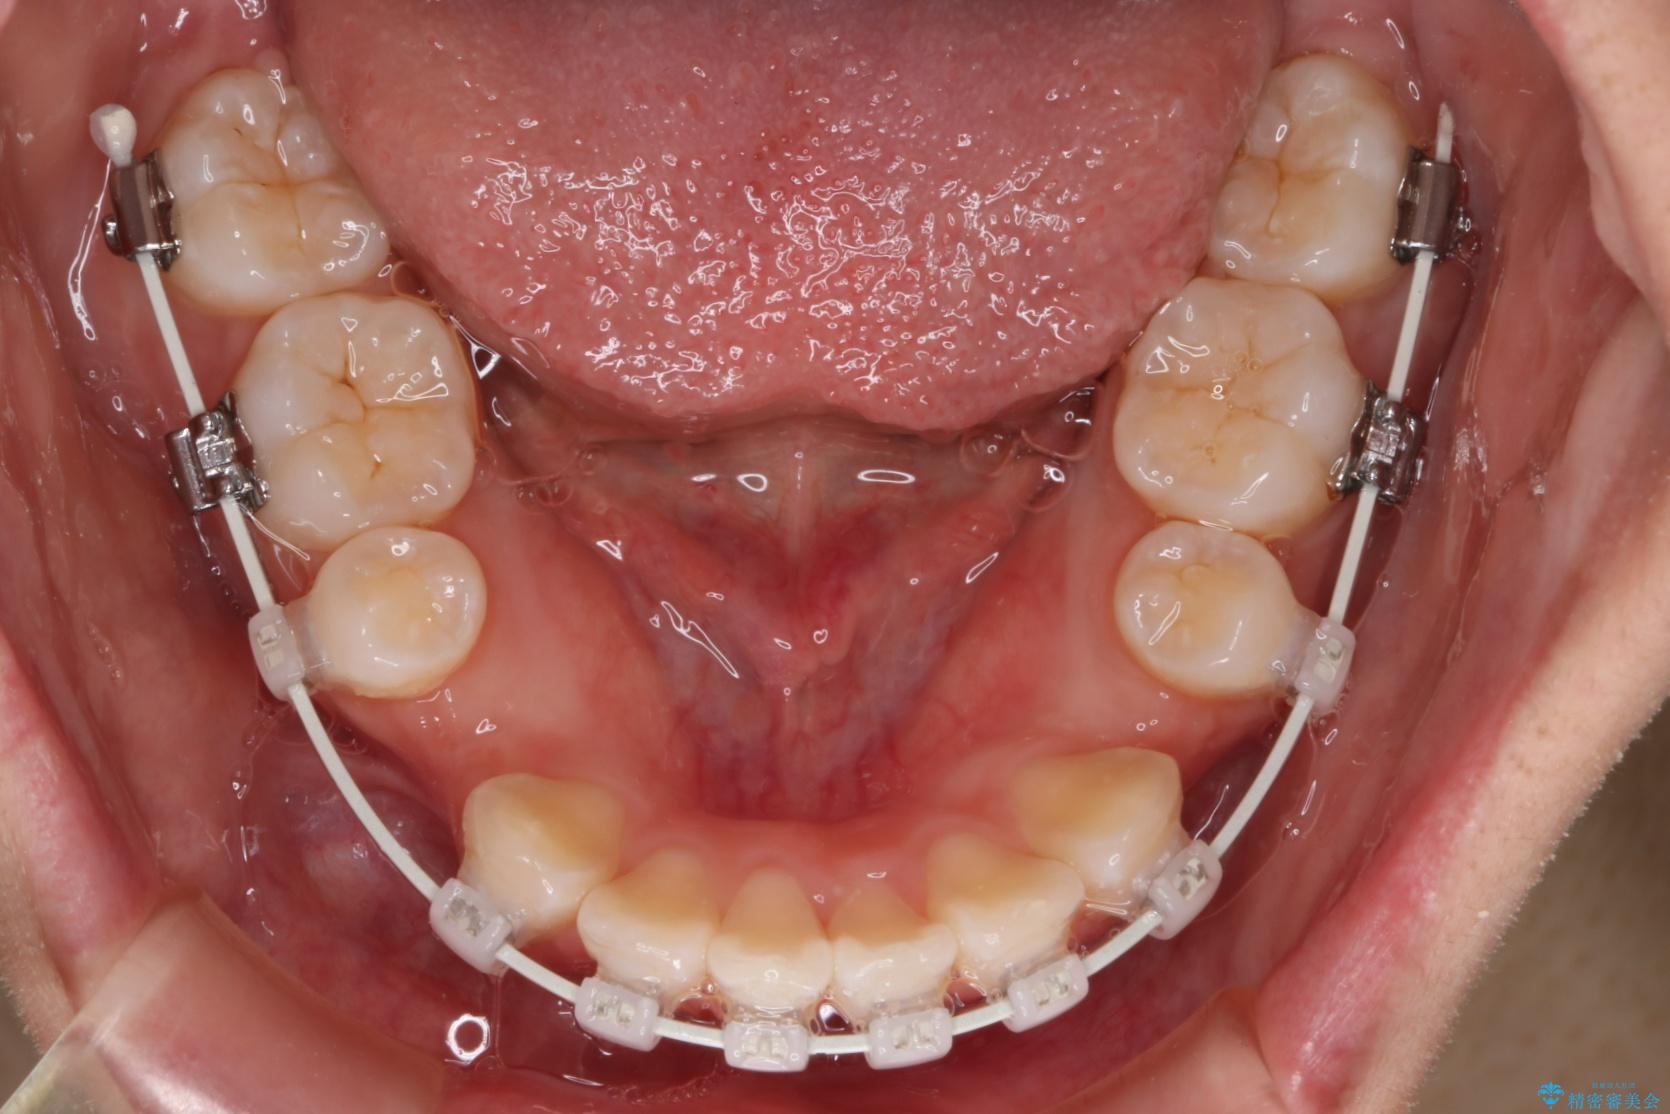

上下4番目の歯を抜歯してガタつきを改善しながら口元を下げる治療計画を立てました。

- 1年9ヶ月

期間も1年9ヶ月と比較的短期間で治療完了することができました。